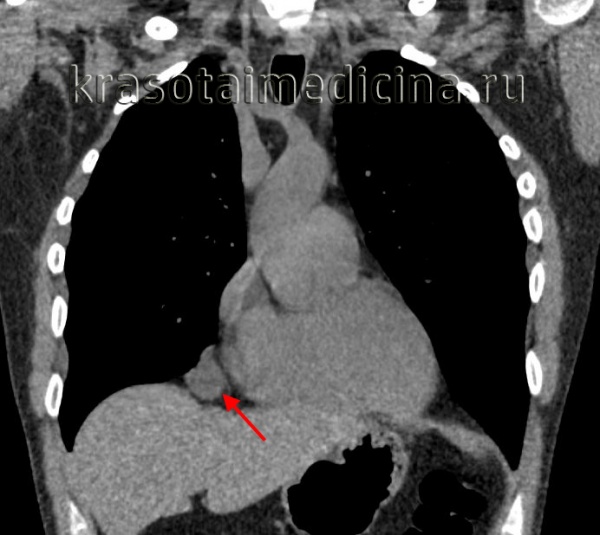

На рентгенограммах по правому контуру сердца у корня легкого определяется тень, располагающаяся в заднем средостении. Пневмомедиастинография (300 мл кислорода) показала, что тень эта локализуется кзади и книзу от корня правого легкого. Диагноз: бронхогенная киста средостения.

На рентгенограмме обнаружена тень, расположенная в медиальных отделах верхушечного, верхнего и частично среднего легочных полей слева. Определяется уровень жидкости с газовым пузырем над ним. Тень локализуется в задневерхней половине средостения. Заключение: нагноившаяся киста средостения.